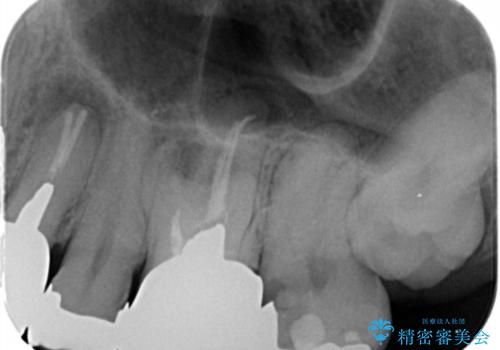

- 銀歯・虫歯・治療途中の歯を治していきたい、セラミックの歯にしたい!と希望され来院されました。

銀歯の下で再発した虫歯や、根尖病変等、多々の問題が認められましたがひとつづつ丁寧に改善し、長期的な予後の見込めるセラミック治療を行っていきます。